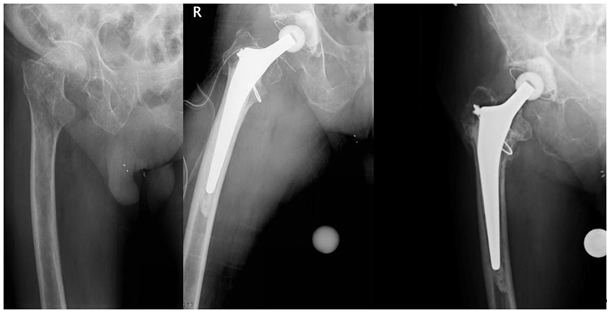

A 77-year old man with a known multiple myelomas fell on his hip and suffered a femoral neck trochanteric fracture (Figure 1). He was administered to our hospital. Due to the type of the fracture (AO 31.B3) as well as a metastasis in the neck and acetabulum a cemented total hip arthroplasty was performed. The greater trochanter was stabilised by cerclage (Figure 1).

Figure 1 Femoral neck trochanteric fracture (AO 31.B3), control after cemented total hip arthroplasty, and follow-up 3.5 years after surgery.

A follow-up CT-scan of the brain was performed 6days after surgery. The ischemia right parietal, in the left thalamus and in the left cerebellum marked clearly. At this time the patient was stable on ward and his neurologic deficits reduced significantly under intensive ergo- and physiotherapy. After two years, the patient returned to our outpatient department after a fall; the hip was stable and no residual neurologic deficits were observed. Upon control three and a half years after the embolism the patient showed no signs of neurologic sequelae and no loosening of the implant (Figure 1).